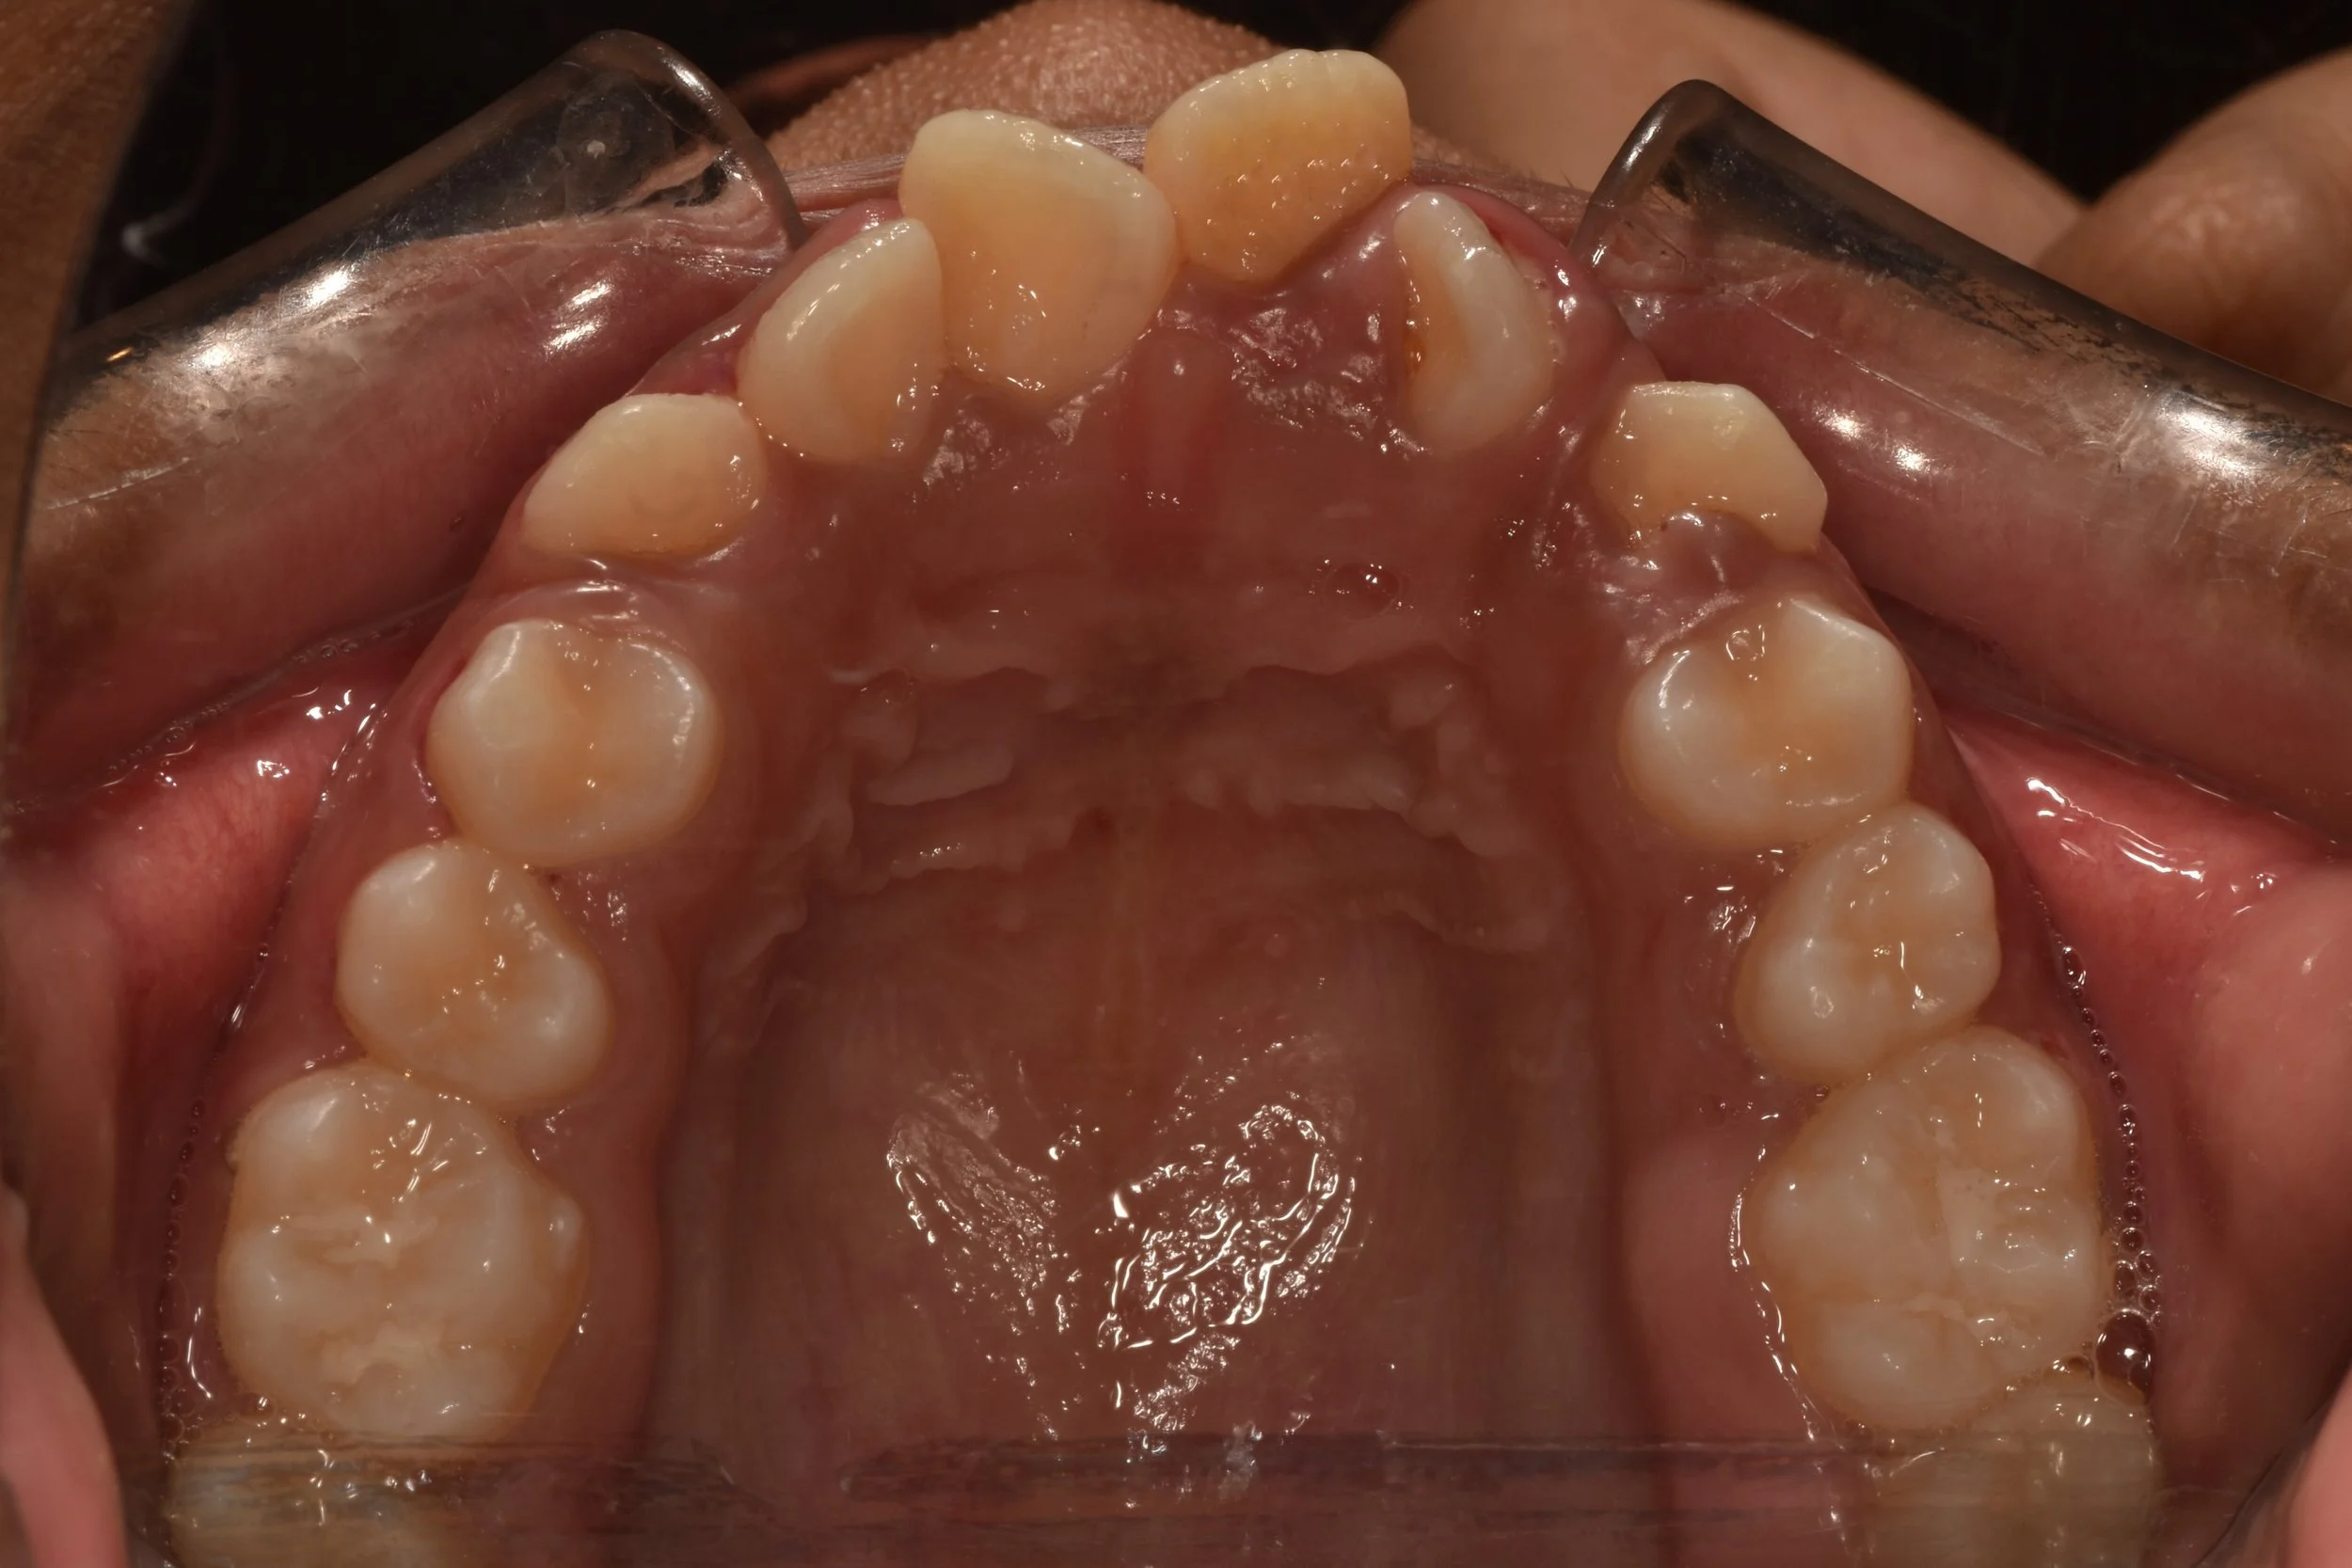

Aligner orthodontics